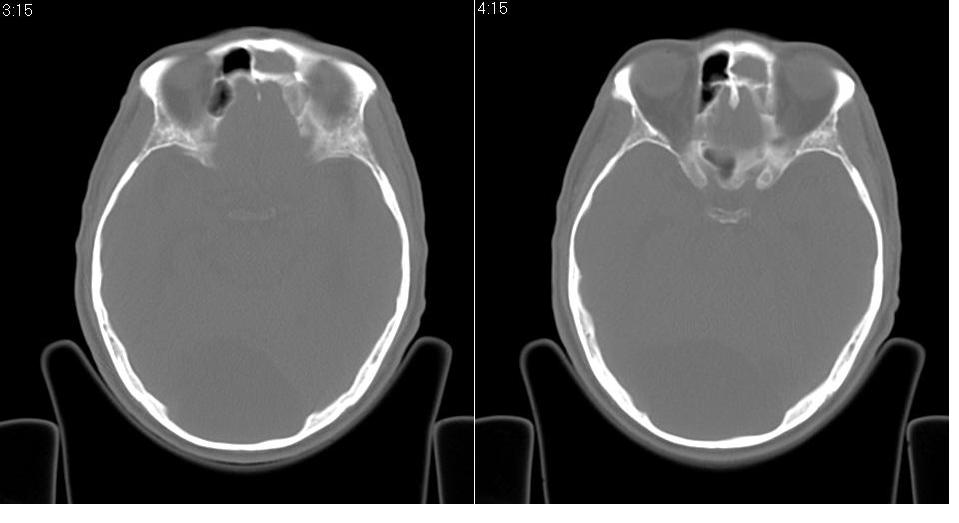

以下是引用zrs在2009-4-21 18:22:00的发言:[br]左侧额窦、筛窦及上颌窦内均充以软组织密度影,且窦壁骨质明显增厚,右侧上颌窦粘膜环形增厚。左侧鼻腔内亦见软组织密度影。考虑慢性鼻窦炎。

以下是引用hnfsh在2009-4-21 19:56:00的发言:[br]病灶主体位于左侧鼻腔内,呈膨胀性生长,鼻中隔、左侧筛板骨质吸收破坏,双侧上颌窦、额窦内聪充满软组织密度影。 考虑:1。左侧鼻息肉 2。慢支副鼻窦炎

以下是引用张xyz在2009-4-21 20:59:00的发言:[br]全组副鼻窦炎并息肉样变[br]